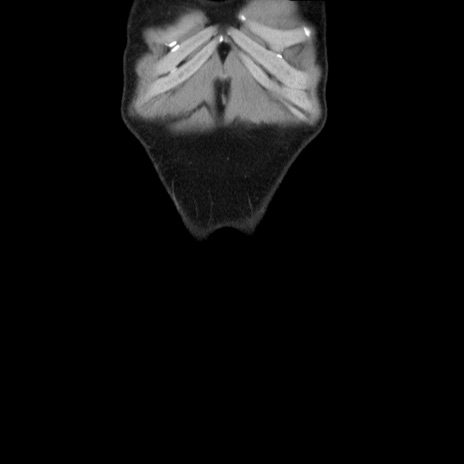

症例36(冠状断像)

【症例】20歳代 男性

【主訴】心窩部痛

【現病歴】今朝より上腹部痛あり。一旦軽快していたが再度出現したため救急要請。昨日夕に白身の魚を含む刺身を食べた。

【身体所見】BP 136/89mmHg、HR 74/min、BT 37.0℃、腹部:膨満、軟、心窩部に圧痛あり。反跳痛なし、筋性防御なし、腸雑音やや亢進あり。

【データ】WBC 17700、CRP 0.48